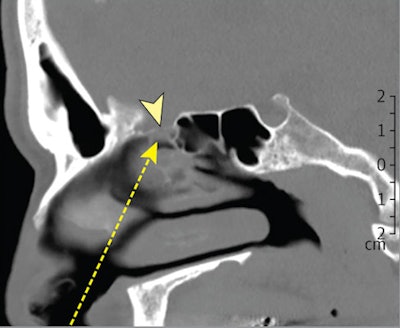

The patient underwent a nasal endoscopy nine months after the onset of his initial symptoms. During the exam, a clear nasal secretion was noticeable between the middle turbinate and the septum on the right side. A CT scan showed a defect in the lamina cribrosa on the right side. A previous brain CT scan from 2011 showed no skull base defect or other pathology.

In December 2020, an endonasal endoscopic closure was performed, and the patient was treated with an antibiotic prophylaxis for seven days following the procedure. The defect in the lamina cribrosa was differentiated from the surrounding mucosa and cleaned. Temporal muscle fascia was used as an underlay graft. Mucosa from the middle turbinate was used as an overlay graft and fixed with fibrin glue.